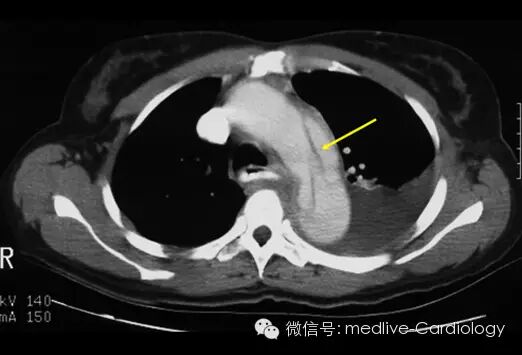

CT扫描是另一种快速而准确的诊断手段,其敏感度和特异度都超过90%。增强CT扫描可以确定夹层扩展范围,观察到将主动脉腔分为两部分的内膜层(黄色箭头),以及识别哪些分支血管血流已中断。采集到的图像还可以到工作站进行三维重建,从而对制定外科手术方案起到辅助作用。后续的检查可以用来观察患者术后情况及评估术后并发症。